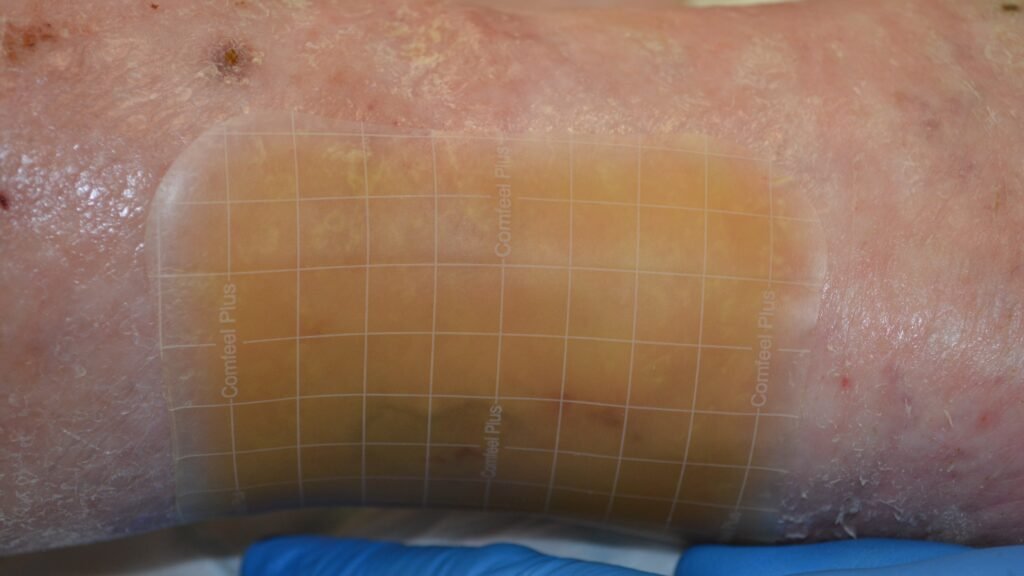

Folien/Filmverbände ohne Saugkissen

Zusätzliche Fotos ![]() 2

2